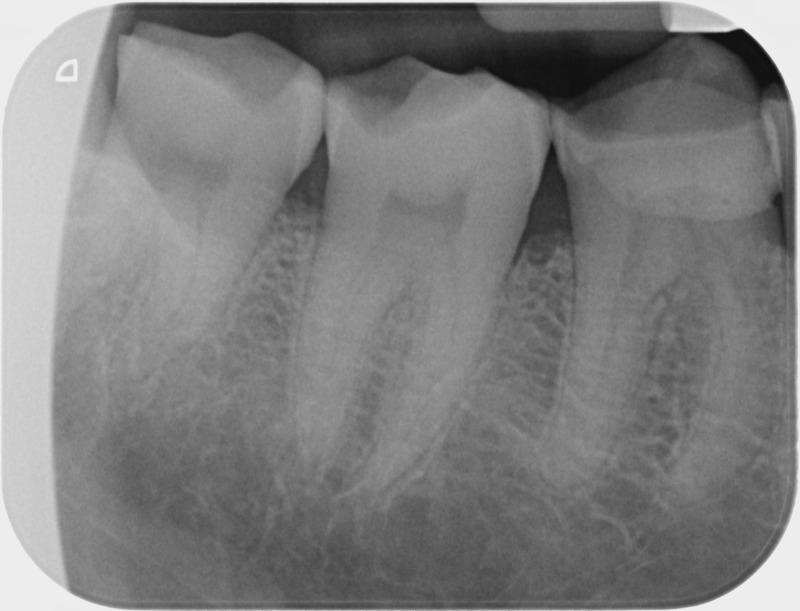

Avant

• Traitement endodontique : Sous anesthésie locale et à travers la protection d’un champ opératoire nous accédons à la pulpe de la dent à soigner, puis aux canaux de ses racines que nous devons désinfecter. Ce soin nécessite l’élimination complète de la source de contamination (souvent la carie) parfois sous une ancienne reconstitution ou une couronne qu’il faut alors retirer. Une fois le nettoyage et la mise en forme des canaux réalisés, nous les obturons de façon hermétique avec un ciment et un matériau thermoplastique appelé Gutta Percha. Ceci afin d’empêcher une nouvelle prolifération bactérienne et d’assurer le maintien de la dent dans ses structures de soutien (ligament parodontal et os alvéolaire). L’ouverture effectuée au centre de la dent sera d’abord refermée avec un pansement provisoire avant d’envisager ensemble la reconstitution d’usage : un composite, un inlay-onlay ou une couronne.